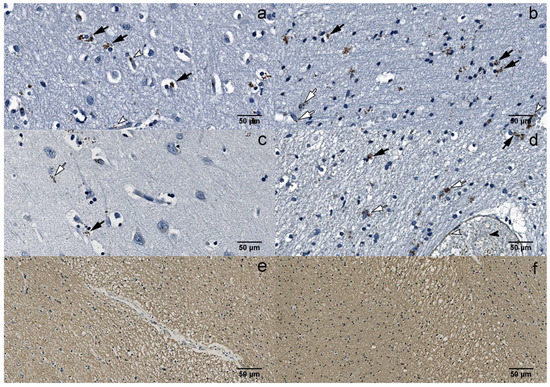

Figure 3. IHC: (a) B19V-positive oligodendrocytes (black arrows) and endotheliocytes (white arrowheads) in the gray matter of the UEP subject (frontal lobe, 400×); (b) B19V-positive oligodendrocytes (black arrows), astrocytes (white arrows) and endotheliocyte (white arrowhead) in the white matter of the UEP subject (frontal lobe, 400×); (c) B19V-positive oligodendrocyte (black arrow) and astrocyte (white arrow) in the gray matter of the UEP subject (temporal lobe, 400×); (d) B19V-positive oligodendrocytes (black arrows), astrocytes (white arrows), endotheliocytes (white arrowhead) and erythrocytes (black arrowhead) in the white matter of the UEP subject (temporal lobe, 400×); (e) myelin basic protein (MBP) immunoexpression in the white matter of the UEP subject (frontal lobe, 400×); (f) MBP immunoexpression in the white matter of the UEP subject (temporal lobe, 400×).

There were significantly (p < 0.0001) more B19V-positive astrocytes in the white and gray matter of the frontal lobe (177 and 147, respectively) compared to the temporal lobe (68 and 64, respectively) in the UEP group (Figure 2e and Figure 3a–d). Similar observations were made in the control group (p = 0.0061 and p < 0.0001, respectively). There were significantly (p < 0.0001) more B19V-positive oligodendrocytes in the white and the gray matter of the frontal lobe (387 and 267, respectively) when compared to the temporal lobe (192 and 128, respectively) in the UEP group (Figure 2f and Figure 3a–d). In the control group, similar observations were made only in the gray matter of the frontal lobe (206 and 139, p = 0.0061).

Multiple demyelinating lesions were detected in the white matter of the UEP group (Figure 3e,f).